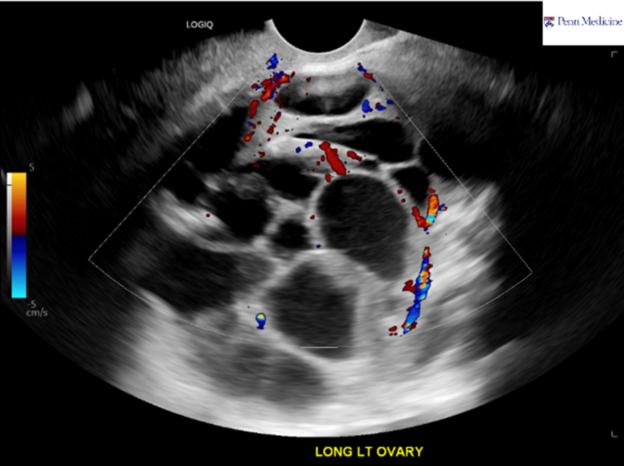

30-year-old woman with pelvic fullness

A 30-year-old otherwise-healthy woman presented for evaluation of pelvic fullness.